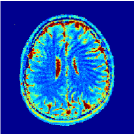

VI-E In-vivo experiments

Two sets of experiments were conducted here: first, we used the 2D and 3D acquisition sequences for scanning a healthy volunteer’s brain (real-world acquisitions). Figures 6 and 7 display the parametric maps reconstructed from 2D spiral and radial readouts. We computed the T1, T2 and proton density (PD) maps using baseline reconstruction algorithms ZF, VS, LR, FLOR, AIR-MRF and our proposed LRTV. While baselines use DM either for quantitative inference or also during reconstruction (i.e. AIR-MRF), we further compare the DM-free LRTV’s performance when cascaded to DM, KM and MRFResnet for quantitative inference. For the 3D spiral acquisitions we compared LRTV and its closest competitor VS in Figure 8. Outcomes from other tested algorithm are displayed in the supplementary materials (Figure S5). Since FLOR does not use dimensionality-reduction, our system ran out of memory during 3D reconstruction; hence results are not reported in this case.

VI-E1 Discussion

The LRTV-DM and LRTV-MRFResnet perform on par, and both outperform all tested baselines for reconstructing T1, T2 and PD maps in all acquisition schemes. This can be observed both visually in Figures 6, 7, 8, S2 and S3, and quantitatively in Table IV across all tested metrics. Other baselines were unable to successfully remove the under-sampling artefacts in TSMIs, and these errors propagated to the parameter inference phase and resulted in inaccurate maps. Temporal-only priors incorporated within LR are shown insufficient to regularise the inverse problem and LR sometimes (e.g. 2D spiral acquisitions) can admit solutions with even stronger artefacts than the model-free ZF baseline. This issue was previously studied for other non-Cartesian MRF readouts that similar to our spiral/radial trajectories, miss to sample the corners of the k-space in all timeframes (see section 2.2.2 and figure 2 in [19]). In the absence of reference for the k-space corners information, the LR iterations despite minimising the objective can converge to solutions with high-frequency artefacts, as visible in the computed maps. This highlights the need for adding an appropriate spatial-domain regularisation. FLOR reduces the LR’s artefacts but this improvement is limited because the suggested nuclear norm penalty does not incorporate an explicit spatial regularisation. Further for reducing artefacts, FLOR can introduce an undesirable bias in the computed T1/T2 maps e.g. see error maps in Figures S2 and S3. The non model-based VS baseline incorporates spatial regularisation and results in spatially smoother maps than ZF and LR, but it is unable to output artefact-free images. Further and consistent with our in-vitro experiment, we observe that VS overestimates the T2 values (e.g. in White and Grey matter regions) in tested 2D acquisitions i.e. the spatial regularisation trades off agains the quantification accuracy. The model-based AIR-MRF adds spatial regularisation through 2D/3D low-pass Gaussian filters however this trades off the sharpness of the computed maps and can increase the errors at the tissue boundaries (we searched Gaussian spreads that keep the blurs and high-frequency artefacts minimal). For our acquisition readouts, Gaussian filters performed better than disk filters of [19] for avoiding strong Gibbs artefacts. On the other hand, the spatiotemporally regularised LRTV greatly improves the TSMI reconstructions i.e. 4 dB enhancement compared to the closest competitor baseline (Table IV). This enables computing accurate and aliased-free multi-parametric inference using DM or the DM-free learning-based alternative MRFResnet as visible in Figures 6, 7, 8, S2 and S3. MRResnet and DM score competitive quantitative inference results i.e. T1 and T2 MAPE less than 5% and 9%, respectively (Table IV). KM also outputs comparably accurate T1 maps, however this shallow learning model despite having a model size larger than MRFResnet, is unable to learn accurate T2/PD quantification and it results in poor estimated maps, consistent with our observations in section VI-C.